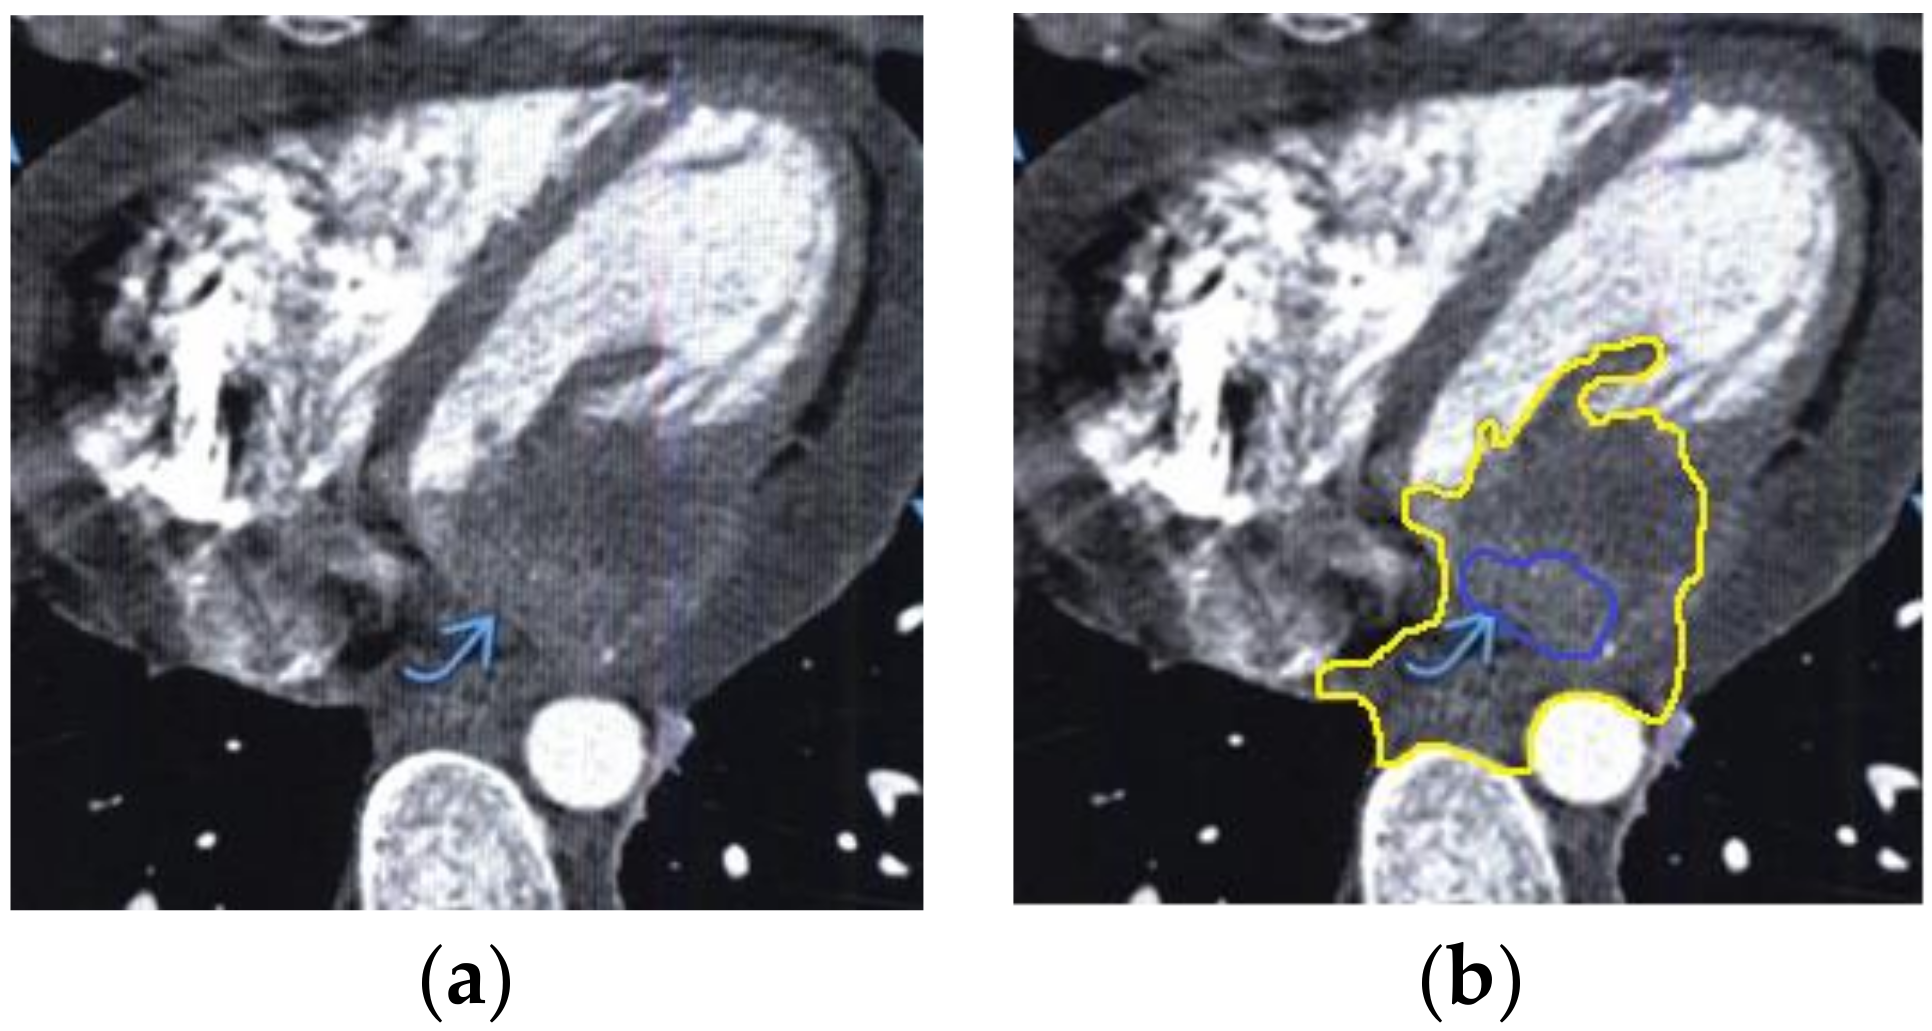

The contour extraction method was used to identify cancerous areas that, after applying the model to eliminate mixed noise, had an increased contrast of volumetric heterogeneous formations in the region of the heart [27]. This method was developed by the authors when analyzing thermal images to assess the condition of the coronary vessels of the myocardium under cardiopulmonary bypass. The contours of the cancerous regions in the examples used for applying the model to eliminate mixed noise (Figure 4, Figure 5, Figure 6, Figure 7, Figure 8 and Figure 9) are highlighted in yellow and they represent the visual boundary of the distribution of volumetric heterogeneous formations.

• For a patient with a history of lung cancer: during MRI with contrast enhancement, the volumetric formation of a heterogeneous structure in the left ventricle was determined (Figure 4).

• For a patient with renal cell carcinoma: during MRI with contrast enhancement in the right ventricle and interventricular septum, the volumetric formation of a heterogeneous structure in the form of infiltrated metastases was determined (Figure 6).

Figure 4. Heart MRI: (a) image with white noise and (b) denoised image with contrast enhancement of volumetric heterogeneous formation.

Figure 6. Heart MRI: (a) image with white noise and (b) denoised image with contrast enhancement of volumetric heterogeneous formation in the form of metastases.